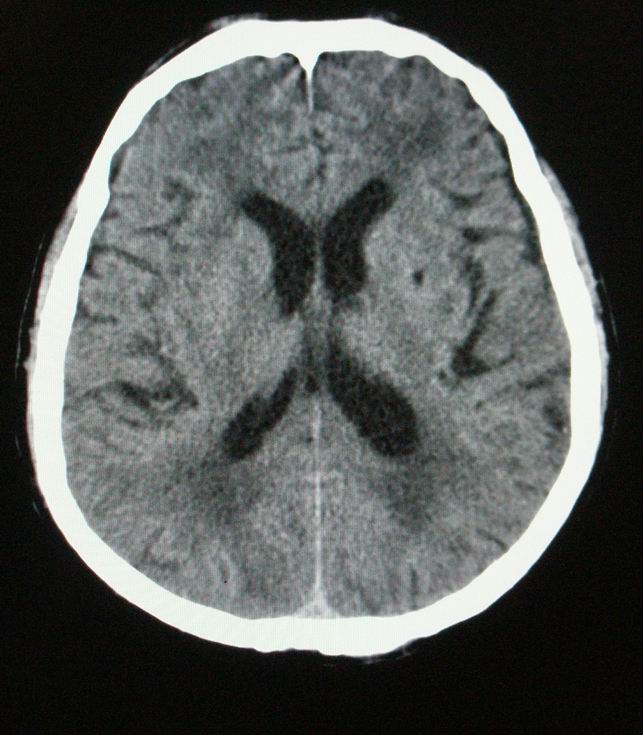

以下是引用随光逐影在2008-4-5 7:46:00的发言:[br]1)考虑为:多发性脑转移瘤。建议:行进一步检查。2)多发性腔隙性脑梗塞。3)脑白质病。4)脑萎缩。

以下是引用zjzjr在2008-4-5 9:00:00的发言:[br]1.双侧颞叶占位性病变,考虑为转移瘤可能性大。[br]2.左侧基底节区陈旧性腔隙性脑梗塞。[br]3.脑白质病。建议mri进一步检查。

以下是引用xuhuihong在2008-4-5 0:59:00的发言:[br]1.双侧颞叶占位性病变,考虑为转移瘤可能性大。[br]2.左侧基底节区陈旧性腔隙性脑梗塞。[br]3.脑白质病。建议mri进一步检查。

以下是引用形影不离在2008-4-4 23:29:00的发言:[br]1.双侧颞叶占位性病变,考虑为转移瘤可能性大。[br]2.左侧基底节区陈旧性腔隙性脑梗塞。[br]3.脑白质病。